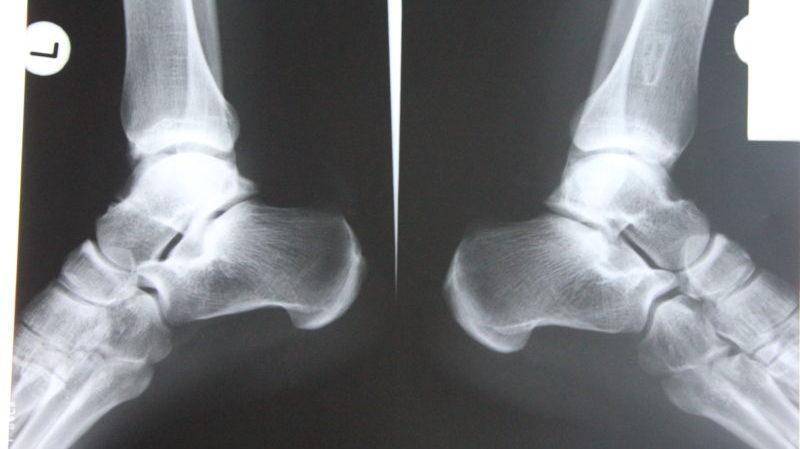

В процессе диагностики и описания производится сравнение полученных снимков с нормой. Проводится описание следующих структур:

- Поверхность кости. Разрушение является признаком сильного воспаления или злокачественных новообразований. Отслоение позволяет заподозрить периостит. Окостенение хрящевой ткани – признак периостоза.

- Костная ткань. Ее увеличение свидетельствует о воспалении или нарушении циркуляции крови, а уменьшение – об атрофии вследствие недостатка физической нагрузки.

- Структура кости. Нарушение целостности является признаком трещины или перелома. Уменьшение костных балок говорит об остеопорозе. Увеличение плотности свидетельствует об остеосклерозе. Рассасывание или некроз кости говорит об остеолизе.

- Суставная щель. Ее сужение – признак артрита, сращение указывает на анкилоз, наличие остеофита – на артроз, расширение – на разрыв связок.

- Стопа. Угол свода больше или меньше 130°, высота больше или меньше 35 мм свидетельствуют о продольном плоскостопии. О поперечном говорит заворот большого пальца.

- Разрыв, растяжение связок. Проводится в 2 проекциях, часто с обезболивающим. Рентген при повреждении связок голеностопного сустава обнаруживает смещение таранной кости, скопление жидкости на участке повреждения, утолщение связок. При разрыве наблюдаются смещение концов кости, увеличение щели, мягких тканей.